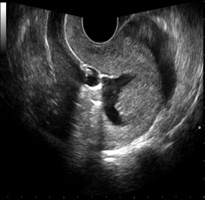

OFollicular Monitoring (फॉलिक्युलार मॉनिटरिंग) सोनोग्राफीच्या मदतीने अंडाशयाची होणारी वाढ बघणे